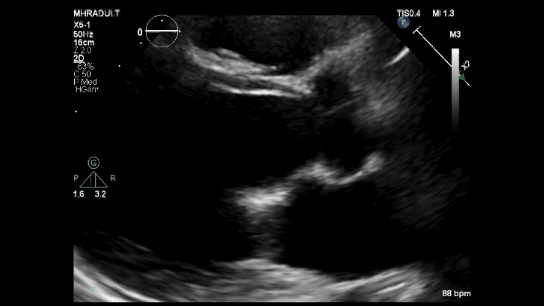

An M-mode echocardiogram from the parasternal long axis demonstrates the "Hammock sign," characterized by a U-shaped abnormal systolic motion and two distinct echoes during systole, representing the anterior and posterior leaflets.